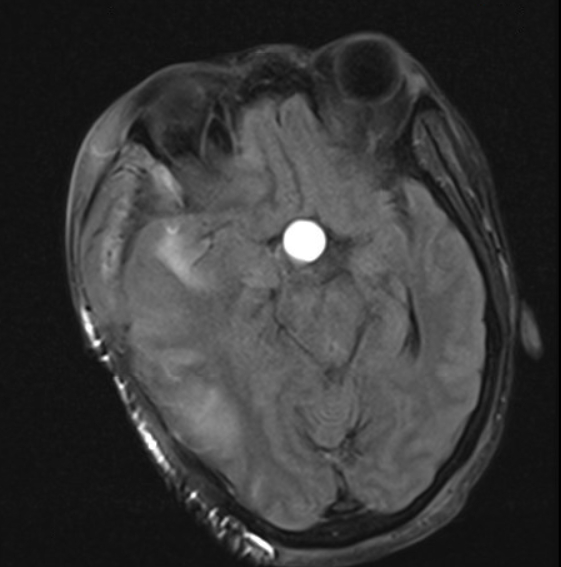

Intervention: The patient was sent to the neurology endovascular catheter lab for diagnostic angiography. The digital subtraction angiography confirmed the distal ICA occlusion with good collateral circulation. Mechanical thrombectomy was attempted, but no clots were aspirated. The stenosis continued to reappear after multiple attempts of balloon angioplasty. The procedure was then terminated as it was concluded that external direct compression was the leading cause of the stenosis. An intravascular stent was placed to prevent complete occlusion. Unfortunately, the patient developed an irreversible right-sided hemiplegia after the procedure. MRI brain demonstrated an evolving infarction of both right MCA and anterior cerebral artery (ACA) territories with concerns for intra-tumoral hemorrhaging in the macroadenoma. The patient was intubated and had an emergent right hemicraniectomy.